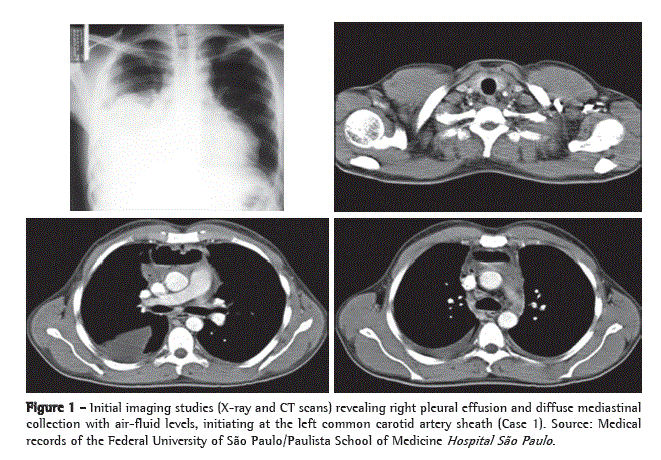

Physical examination on admission to the emergency room revealed pallor (2+/4+); tachypnea (22 breaths/min); normal blood pressure (110 × 60 mmHg); cervical edema and phlogosis; dullness to percussion over the base of the right hemithorax (RHT); absent breath sounds in the middle and lower third of the RHT; and tachycardia (124 bpm). However, cardiac auscultation revealed no abnormalities. General laboratory tests showed leukocytosis (16,900/µL), with 9% rods and 81% neutrophils, thrombocytosis (756,000/µL), increased levels of C-reactive protein (225.9 mg/L), and increased ESR (92 mm/h). A chest X-ray revealed upper mediastinal widening, opacification of the lower two thirds of the RHT, and enlarged cardiac silhouette. The patient subsequently underwent CT of the neck and chest, which revealed large gaseous collections, initiating at the cervical region and extending along the left carotid sheath, spreading into the anterior and middle mediastinum, the pericardium, and the right pleural cavity (Figure 1).

We opted for therapy with broad-spectrum antibiotics (imipenem, cilastatin, and vancomycin) and emergency surgical exploration. The patient was placed in a semi-seated position, with outstretched arms, and his RHT was elevated 30° with the use of cushions. We opted for simple orotracheal intubation. We began with collar cervicotomy at the level of the cricoid cartilage to explore cervical compartments and continued to explore up to the base of the mandible, from where the infectious focus originated. Subsequently, we performed a 1.5-cm thoracotomy incision in the seventh right intercostal space (RIS), introduced a 10-mm fiberoptic bronchoscope (30°), and performed a 6.0-cm accessory anterior minithoracotomy incision in the fourth RIS, through which the entire pleural cavity was cleaned, the mediastinal pleura was opened, and all purulent fluid was drained. We placed an 18 F tube (airtight seal) in the anterior mediastinum and two tubes (water seal) in the pleural cavity-a posterior 18 F tube and an anterolateral 28 F tube. In the cervical region, we placed a Penrose drain, creating communication between the surgical site and the anterosuperior mediastinum, as well between the surgical site and the right pleural cavity, through the pretracheal fascia. Subsequently, the patient was referred to the ICU, where he remained under mechanical ventilation and received low doses of vasoactive drugs. The evolution was favorable, mechanical ventilation and the use of vasoactive drugs were discontinued on postoperative day 2, and the patient was discharged from the ICU on postoperative day 3 (Figure 2). The patient was